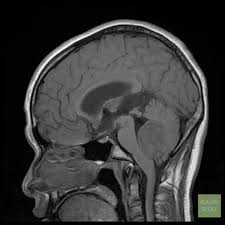

Distended dural venous sinuses with venous distension sign present on the sagittal t1 images. A ventriculoperitoneal vp shunt is a medical device that relieves pressure on the brain caused by fluid accumulation. Appearances are consistent with intracranial hypotension secondary to csf overshunting.